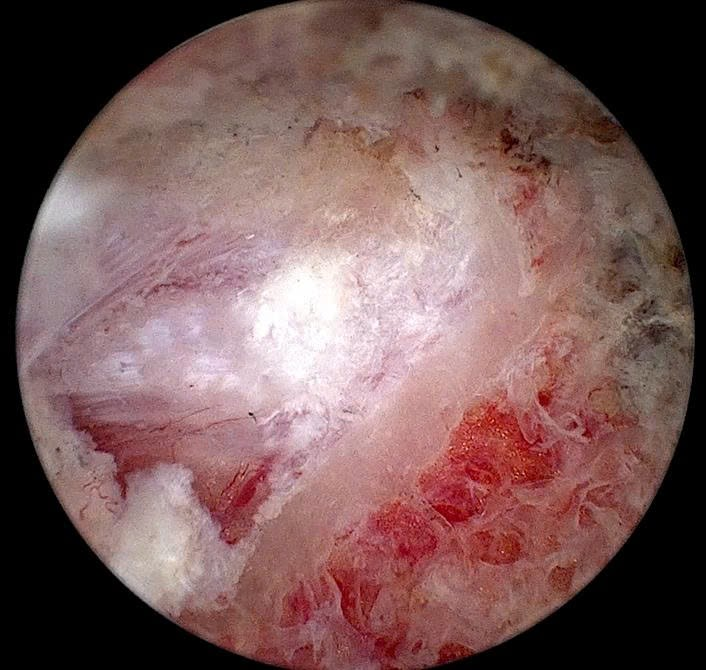

Ca phẫu thuật của bệnh nhân T. diễn ra thuận lợi và an toàn, dưới sự phối hợp của ê-kíp Gây mê hồi sức và các bác sĩ khoa Ngoại Chấn thương.

Hình ảnh tủy sống và rễ thần kinh được bộc lộ dưới camera nội soi

Theo chia sẻ của Ths. Bác sĩ Trần Bình Ngọc – Trưởng khoa Ngoại Chấn thương, Bệnh viện A – Người trực tiếp thực hiện ca phẫu thuật: “Kỹ thuật nội soi cột sống thắt lưng hai cổng điều trị thoát vị đĩa đệm hiện được xem là một trong những kỹ thuật xâm lấn tối thiểu tiên tiến trong điều trị các bệnh lý cột sống. Với hai đường rạch nhỏ khoảng 5–10mm, giúp bảo tồn tối đa cơ cạnh sống và cấu trúc cột sống. Camera độ phân giải cao hỗ trợ phẫu thuật viên quan sát rõ, bóc tách chính xác khối thoát vị và hạn chế nguy cơ tổn thương thần kinh, mang lại hiệu quả điều trị cao so với phẫu thuật mổ hở truyền thống. Ngoài ra, phương pháp này còn giúp bệnh nhân ít đau sau mổ, phục hồi nhanh, rút ngắn thời gian nằm viện”.